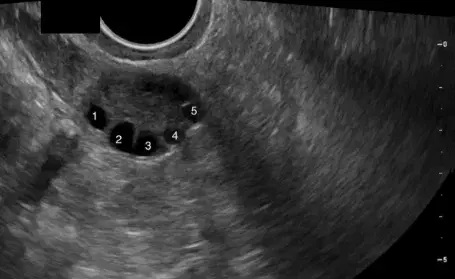

Ovarian Antral Follicle Evaluation Course